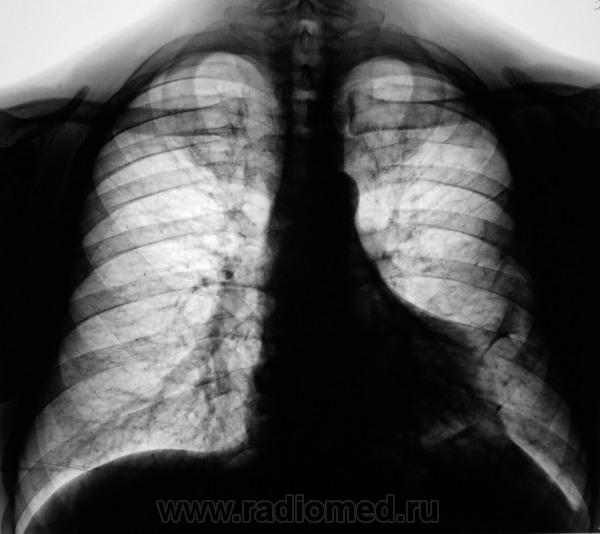

Уменьшение пневматизации нижней доли, плевро-медиастино-диафрагмальные спайки, деформация диафрагмы, средостения-больше данных за посттравматические изменения органов грудной клетки, + диафрагмальная грыжа.

Нарушение проходимости "среднедолевого или их?" бронха слева, гиповентиляция язычковых сегментов, тень в верхнем средостении. Центральный рак.